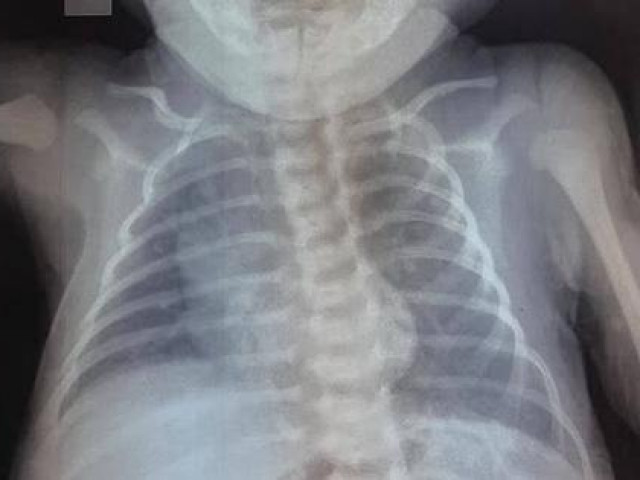

Hành trình đầy khó khăn, thử thách nhưng các y, bác sĩ của Trung tâm Hồi sức tích cực bệnh nhân COVID-19 Bệnh viện Đại học Y Dược TPHCM đã làm nên điều kỳ diệu, với sự nỗ lực, quyết tâm, mẹ con thai phụ mắc COVID-19 nặng đã được cứu sống ngoạn mục.

Sản phụ mắc COVID-19 được cứu sống ngoạn mục sau 45 ngày nguy kịch

Đây là ca bệnh đầu tiên tại Đồng Nai áp dụng kỹ thuật tim phổi nhân tạo ECMO được xuất viện.